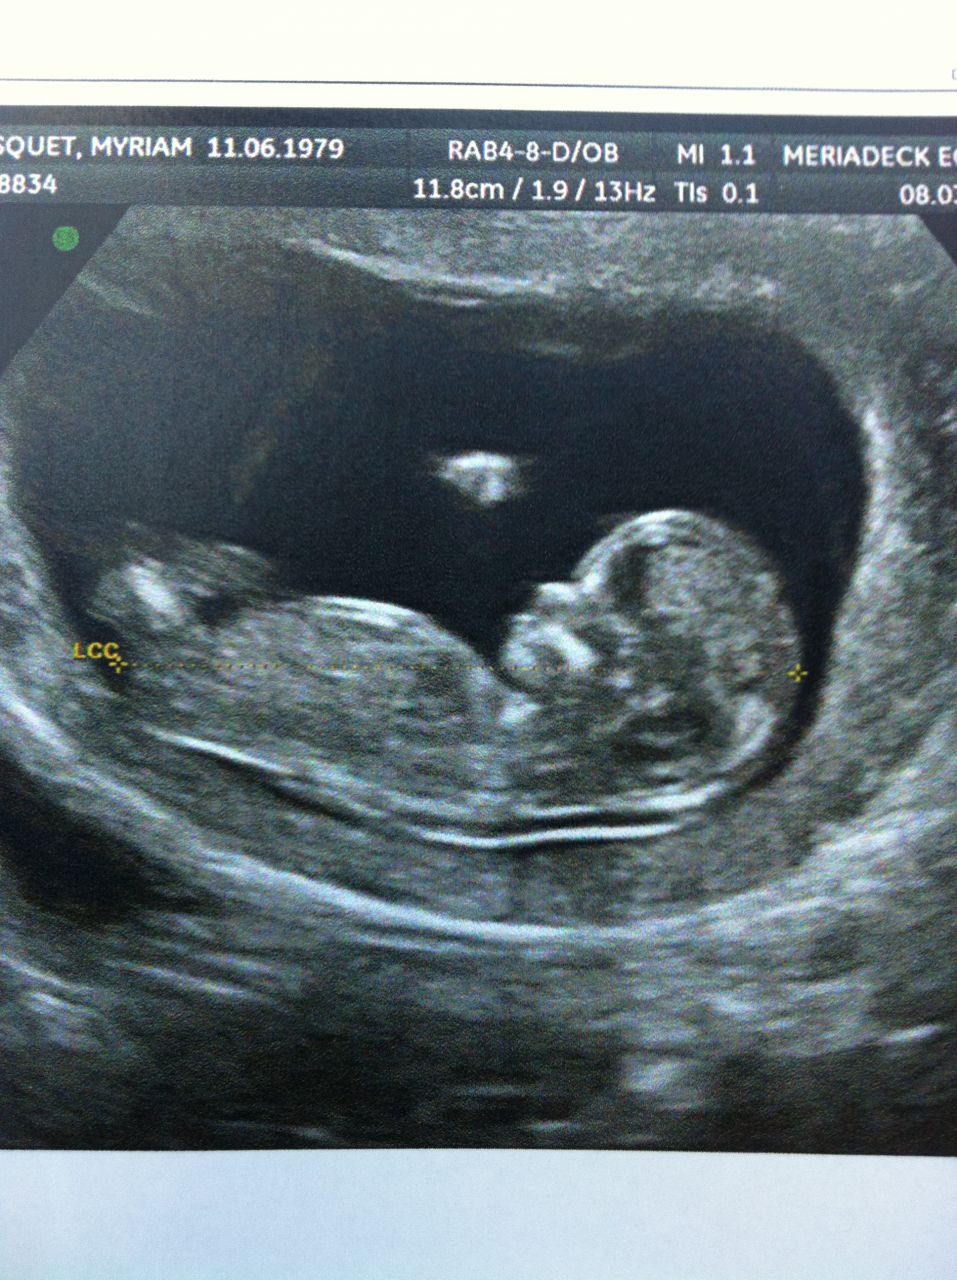

| Dire merci | Coucou les filles ! bon je reviens de mon écho et tout va bien ! bébé 2 mesure 6,6 cm de la tête aux fesses Ce soir on l'annonce à mon grand Mon bébé 2 en image ![]() |

| Dire merci | Journée de la femme aujourd'hui au boulot, très sympa. On a fait resto et bowling c'était cool. MYRIAM Super ton écho, on voit bien !! Message édité le 08/03/11 à 18:03 Message édité le 08/03/11 à 18:15 |

| Dire merci | facettie je la trouve très sympa la robe que tu t'es deniché !! Je dirais même que je regrette encore plus de pas encore être enceinte elle est canon !! Myriam, trop chouette ton écho on voit deja bien les détails !! Je me languis de connaitre la réaction de ton petit homme quand il va apprendre la nouvelle Ah oui et puis toutes les baveuses sans cervelles qui viennent sous mariner sur le post : "des nanas qui n'arrivent pas à tomber enceinte et qui ont du coup un peu de mal à poster car c'est pas évident de trouver sa place au milieu de plein de femme enceinte ravies. Si il régnait une telle ambiance ici ca ferait très longtemps que je ne posterais plus et d'autres aussi qui sont dans la même galère !! Ben oui j'avoue haut et fort qu'après quasi 2 ans d'essai ca fat du bien de se sentir comprise, écouté et soutenue !!! |